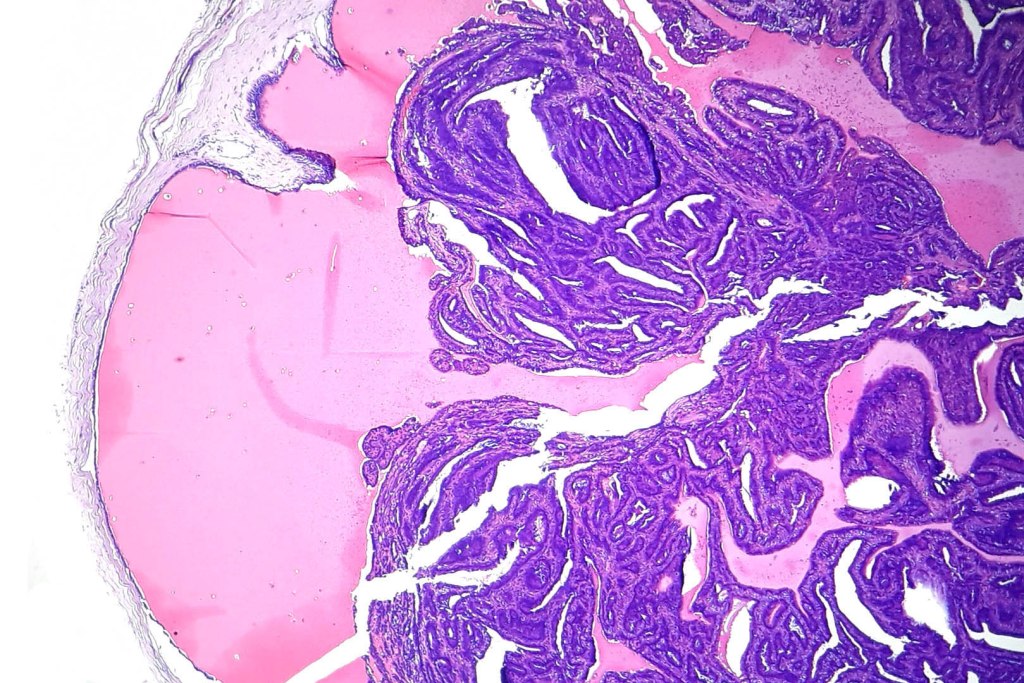

•Circumscribed intradermal/lamina propria nodule

•Cystic or solid